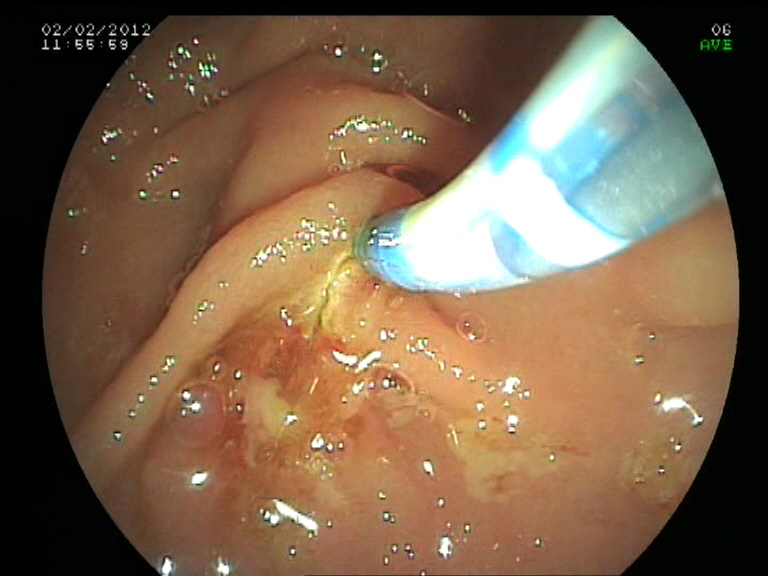

Ictericia obstructiva por cáncer de cabeza de páncreas: canulación con NK en un 2º tiempo y drenaje con prótesis metálica recubierta

Paciente de 74 años de edad con diagnóstico de neoplasia de cabeza pancreática irresecable tras realización de ECO, TAC abdominal USE-PAAF (estadio T3N3M0; IIIB) e ictericia obstructiva asociada. Se decide realizar drenaje con CPRE, usando varias técnicas de canulación de forma secuencial: canulación estándar, precorte con esfinterotomo de aguja asociado a una esfinterotomia transpancreática tipo 2, todas fallidas. Finalmente se decide demorar la técnica en unos días, consiguiendo la canulación de forma sencilla y drenando la vía biliar con una prótesis recubierta de 6 cm metálica (Wallflex biliar).